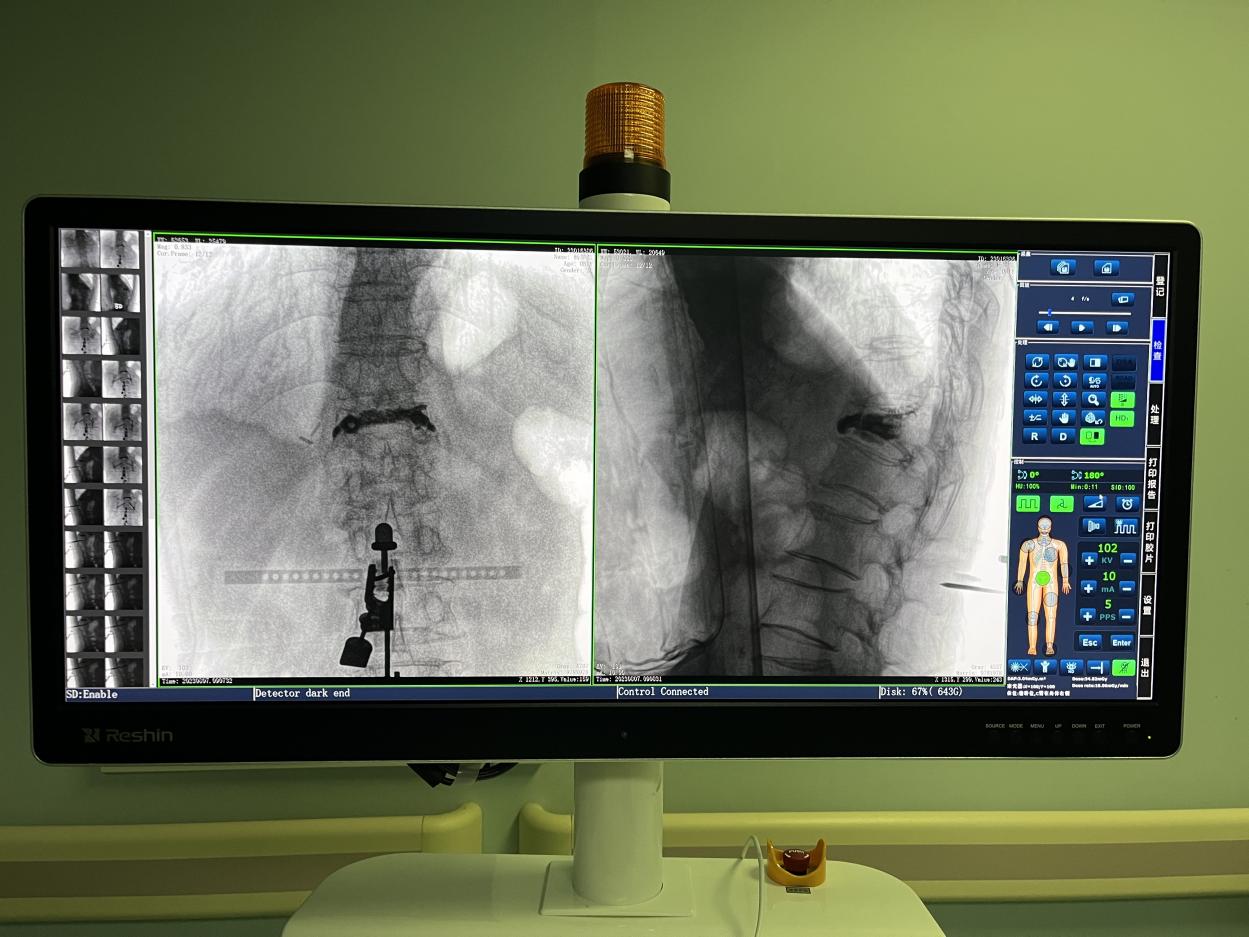

骨科機(jī)器人手術(shù)-術(shù)后影像

目前,普愛(ài)醫(yī)療骨科手術(shù)機(jī)器人已在江蘇省人民醫(yī)院、南京醫(yī)科大學(xué)第二附屬醫(yī)院等多家醫(yī)院投入使用,臨床反饋良好,幫助醫(yī)患降低手術(shù)風(fēng)險(xiǎn)的效果顯著。